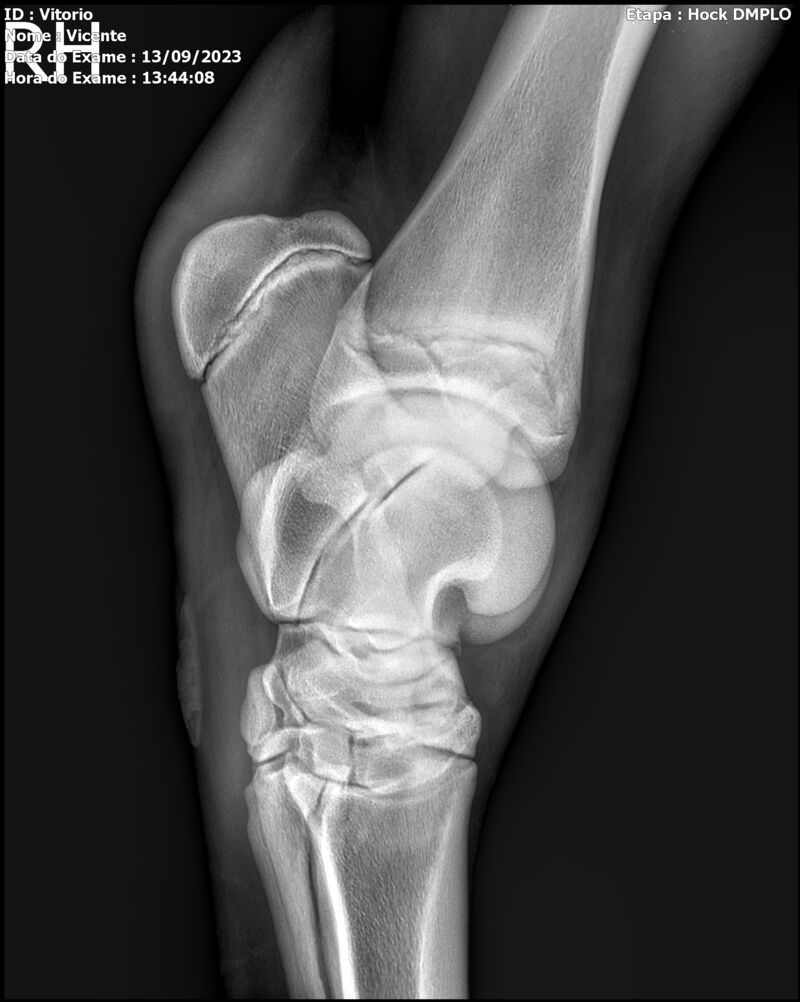

LOTE 13

THUNDER ZC

Raça: BRASILEIRO DE HIPISMO

Sexo: MACHO - POTRO

Nascimento: 17/09/2022

Altura Aproximada: 1,54

Pel.: CASTANHO

Registro: EM AND

Vend.: VICENTE CONTE

Local : PORTO FELIZ/SP